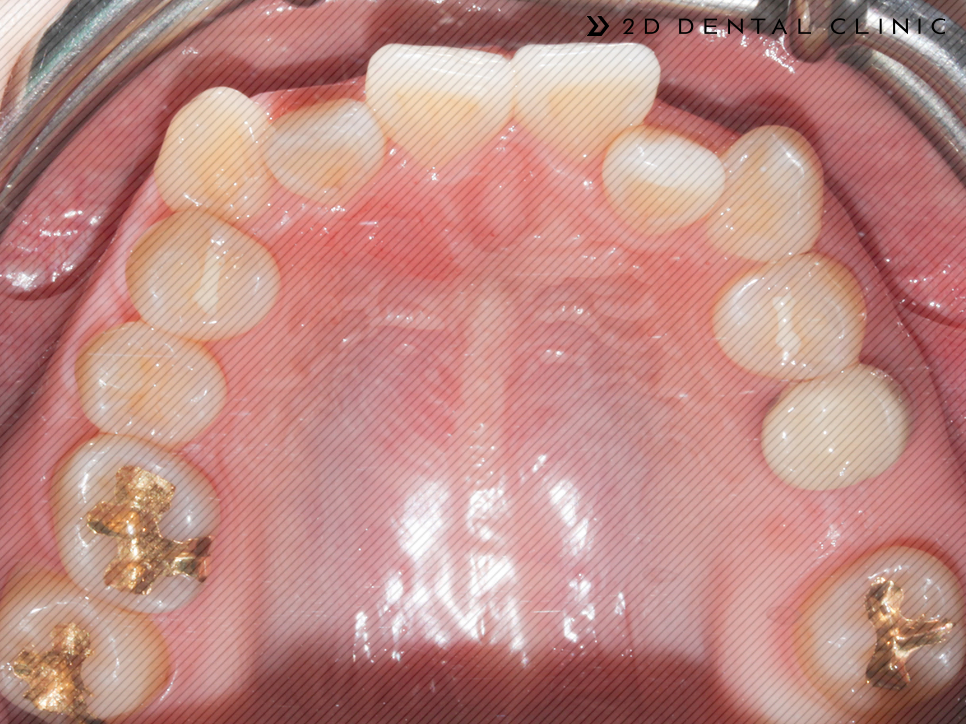

전체적인 크라우딩의 개선

교정기간은 1년 반이 소요되셨답니다~ 전체적인 크라우딩이 개선되고 치아 배열이 고르게 개선되었습니다.

코와 턱 이어지는 E라인을 잡아드려 퉁명스러울 수 있는 인상이 개선됨이 보입니다.